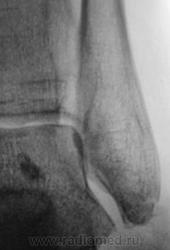

Трах... и вырос "грибок" на таранной...

Грибок этот не "трахогенной" природы. У меня вообще сомнения, что это вырост кости.

Лодыжка срастется, никуда не денется. А вот оссифицирующий апоневрозит и данный то-ли экзостоз, то-ли оссификат капсулы будут периодически доставать и пациента, и врача-куратора.

Больше склоняюсь к хондромному телу, хоть в данном месте не встречал

Грибок этот не "трахогенной" природы. У меня вообще сомнения, что это вырост кости.  +1 !     Больше похоже на обызвествление сосудов . А хондроматоз - не подходит по локализации , хотя сама тень похожа внешне .